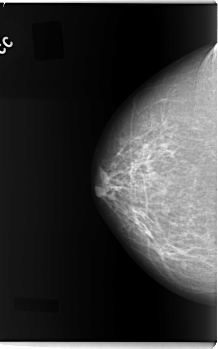

C_0088_1.LEFT_MLO

LEFT_MLO LINES 5864 PIXELS_PER_LINE 3504 BITS_PER_PIXEL 12 RESOLUTION 50 OVERLAY